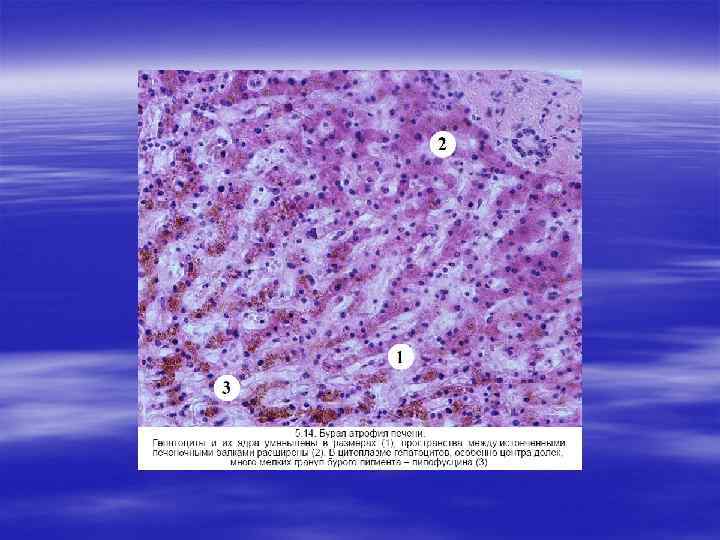

ВТОРИЧНЫЕ НЕФРОСКЛЕРОЗЫ § Поражение почек любой этиологии в итоге ведет к почечной недостаточности, структурной основой которой является нефросклероз. Нефросклероз представляет собой патологический про цесс, сопровождающийся разрастанием фиброзной ткани с уплот нением и сморщиванием почек. Поверхность почек приобретает зернистый или бугристый характер. В зависимости от причин выделяют две основные группы нефросклероза: первичное и вто ричное сморщивание почек.

§ Основными причинами первичного сморщивания почек явля ются гипертоническая болезнь и атеросклероз сосудов почек. Причем гипертоническая болезнь ведет к развитию артериолосклеротического нефросклероза, а атеросклероз — к атеросклеротическому нефросклерозу.

§ Вторичное сморщивание почек развивается в исходе различных воспалительных, дистрофических и иммунопатологических процессов, развивающихся в них: § 1) хронических гломерулонефритов, § 2) хронического пиелонефрита, § 3) амилоидоза почек, § 4) мочека менной болезни, § 5) туберкулеза почек, § 6) диабетического гломерулосклероза.

§ Нефросклероз любой этиологии приводит к терминальной почечной недостаточности, характерным клиническим признаком которой является уремия. § Уремия — это синдром аутоинтоксикации, разбивающейся в ре зультате задержки в организме азотистых метаболитов и других токсических веществ, нарушения водно солевого, кислотно щелоч ного и осмотического гомеостаза.